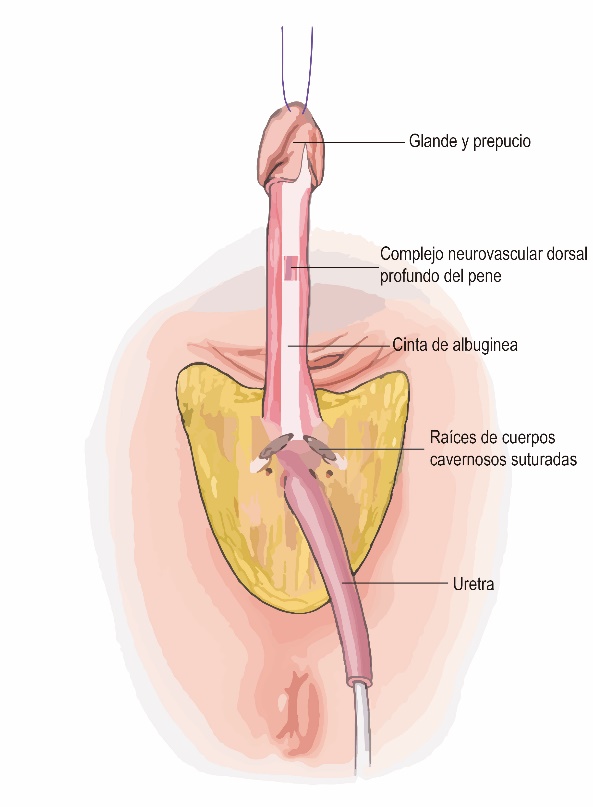

- Segmento de glande y prepucio junto al complejo neurovascular dorsal profundo del pene (Figura 1) permitirán crear el neo clítoris, el capuchón y la cara interna de los labios menores.

- Cuerpos cavernosos que se resecan a nivel de las cruras bajo las ramas isquio-pubianas (Figura 1).

- Uretra, resecando la mayor parte de la uretra peneana, así como los músculos bulbo esponjosos y parte de la esponja bulbar para crear un neo meato espatulado que permita orinar sentada (Figura 2).